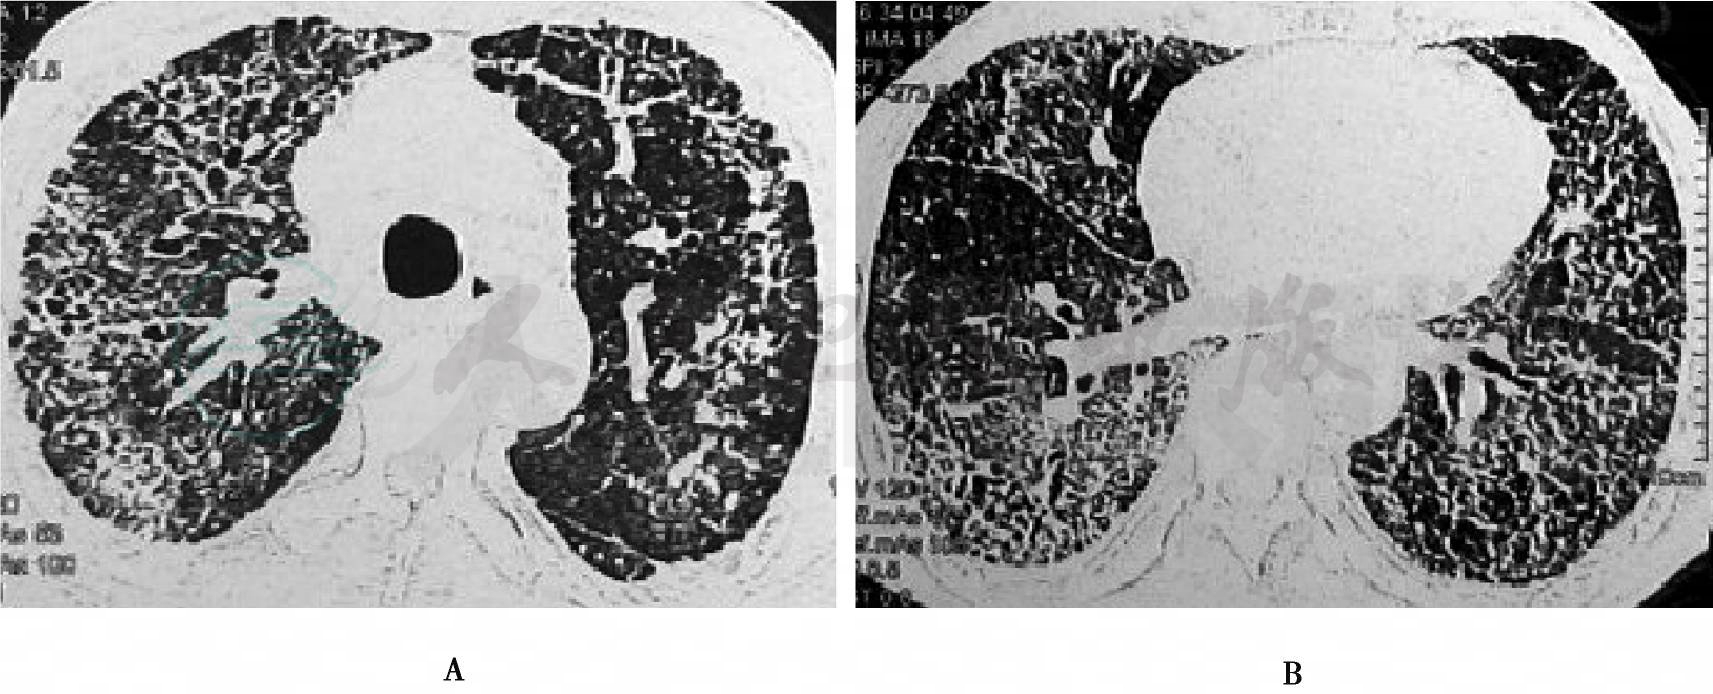

患者,男性,59岁,农民,主因“咳嗽咳痰,活动后气促3个月余”于2009年3月16日第一次收住我科,入院后查血清抗核抗体(ANA)(+,1∶20,均质型);抗中性粒细胞胞浆抗体(ANCA)(+,胞浆型);血管炎三项:抗髓过氧化物抗体(MPO)(+),抗蛋白酶3抗体(PR3)、抗基底膜抗体(GBM)均阴性。肺部CT(图1)示双肺呈蜂窝状、网格状改变并感染,双侧胸膜增厚及粘连。经纤支镜下肺活检示肺间质纤维化,肺泡壁增厚,轻度慢性炎症,未见血管炎病变,抗酸及PAS染色阴性,未见血管炎改变。结合临床最后诊断为特发性肺纤维化合并感染。予以左氧氟沙星抗感染控制感染后,予泼尼松30mg/d口服,患者病情好转。出院后,患者坚持口服泼尼松30mg/d,2个月;20mg/d,1个月;15mg/d,1年。2009年7月8日复查肺部CT(图2)较前无明显好转。2010年7月患者自觉症状改善停用泼尼松。患者因受凉、劳累后出现咳嗽咳痰,活动后气促,间断发热,于2010年10月11日第二次收住我科。起病后,患者精神、食纳较差,二便正常。既往史无特殊,其弟弟2009年也因气促,经肺CT诊断为双肺间质病变。

图1 肺CT(2009-02-20)

图2 肺CT(2009-07-08)

患者2009年3月第一次在我科住院时,门诊肺部高分辨CT示双肺呈蜂窝状、网格状改变;无药物及职业相关病史;入院后予查自身免疫性疾病相关抗体,示ANCA阳性;为排除血管炎等结缔组织疾病,进一步行支气管镜下肺病理活检,病检结果示肺间质病变,未见血管炎改变。最后结合临床,诊断为特发性肺纤维化。予以抗感染及激素治疗后,患者病情稳定,出院后继续坚持服用激素治疗。于2010年7月在当地复查肺部CT示病变明显吸收后停用激素。此次为受凉后复发,并出现新发咳嗽咳痰,发热等急性症状,血象升高,结合入院后床旁胸片考虑双肺间质病变合并感染,予以N-乙酰半胱氨酸抗纤维化,哌拉西林/他唑巴坦4.5g每8小时一次抗感染治疗,并于10月14日起予以甲泼尼龙40mg/d静滴治疗原发病,同时考虑患者长期使用激素,感染高危宿主,不排除卡氏肺孢子虫感染,予复方磺胺甲𫫇唑片1.0g每日3次治疗8天后,患者病情较前无明显改善,复查床旁胸片示肺部原发病变较前扩大,遂于10月19日改为亚胺培南0.5g每6小时1次、甲泼尼龙120mg静滴加强抗炎。患者症状逐渐好转,10月20日复查肺部CT(图5)示小叶间隔增厚呈网格状、磨玻璃样改变,内夹粟粒样小结节及斑片状影,以肺外围及胸膜下明显,双肺弥漫性间质性病变,与患者前片比较肺部感染较前有吸收,但双肺间质病变较前加重。10月28日因家有急事要求签字出院,遂带药出院。患者出院后1天病情加重,在当地医院因呼吸衰竭抢救无效死亡。